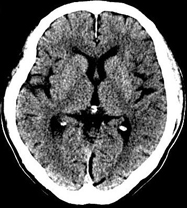

如上圖所示,相鄰的三張軸位圖像未見明顯異常,根據(jù)傳統(tǒng)軸位圖像很難得到準確的臨床診斷。

同一病人利用容積數(shù)據(jù)進行三維處理后,高品質MPR和三維圖像上則清晰顯示了縱向排列的腹腔干與腸系膜上動脈相鄰近,血管發(fā)生變 異,近端血管閉塞,為臨床提供了精確的診斷信息。

從上面的例子可以看到,能否為臨床提供高品質的三維影像成為了16層CT的核心價值,而東芝新一代的 全景三維16層CT擁有最為  先進的3項核心技術,在16層核心價值上的表現(xiàn)自然值得期待。